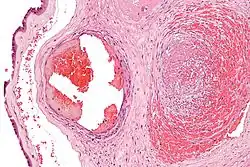

Excessive generation of fibrin due to activation of the coagulation cascade leads to thrombosis, the blockage of a vessel by an agglutination of red blood cells, platelets, polymerized fibrin and other components. Ineffective generation or premature lysis of fibrin increases the likelihood of a hemorrhage.

When the lining of a blood vessel is broken, platelets are attracted, forming a platelet plug. These platelets have thrombin receptors on their surfaces that bind serum thrombin molecules,[1] which in turn convert soluble fibrinogen in the serum into fibrin at the wound site. Fibrin forms long strands of tough insoluble protein that are bound to the platelets. Factor XIII completes the cross-linking of fibrin so that it hardens and contracts. The cross-linked fibrin forms a mesh atop the platelet plug that completes the clot. Fibrin was discovered[2] by Marcello Malpighi in 1666.[3]